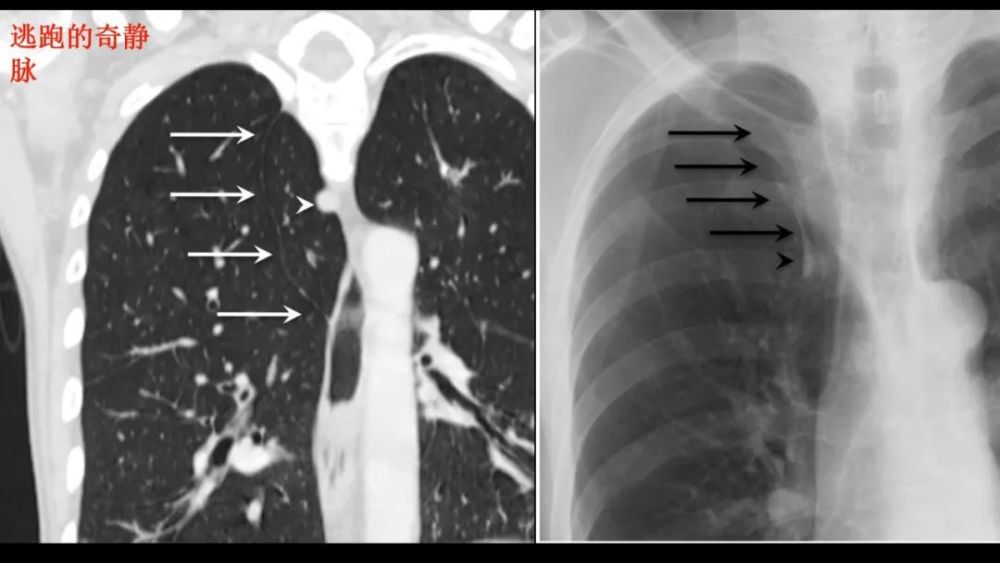

奇 裂

奇静脉分隔右肺上叶尖段

不是真正的附叶 , 因为没有自己的支气管 解剖标本的发生率为1% , M:F=2:1

X:细线状隆起(相对于纵膈) , 穿过右肺尖 , 前位上纵膈胸片可?气体

CT: 奇裂从SVC和气管后穿过